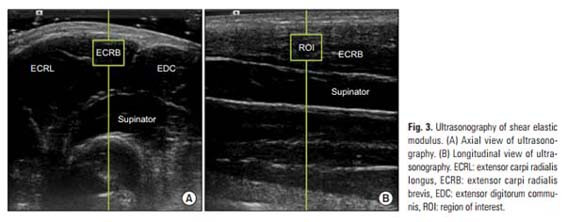

Á¤Çü¿Ü°ú ¼ö¼ú °ü·Ã SCOPUS±Þ ±¹Á¦ÇмúÁöÀÎ ¡®Clinics in Orthopedic Surgery¡¯¿¡ °ÔÀçµÈ ¡®What Is the Most Effective Eccentric Stretching Position in Lateral Elbow Tendinopathy¡¯ ³í¹®Àº Å״Ͻº ¿¤º¸¿ì¿¡¼ Áõ»óÀ» È£Àü½ÃŰ´Â ½ºÆ®·¹Äª ¹æ¹ý¿¡ ´ëÇÑ ¿¬±¸·Î °¡Àå È¿À²ÀûÀÎ ¿îµ¿ÀÚ¼¼¿¡ ´ëÇØ ź¼º ÃÊÀ½ÆÄ¸¦ ÀÌ¿ëÇÑ °á°ú¸¦ º¸°íÇÑ ³í¹®ÀÌ´Ù.

| | ¡è¡è ¡ã½ºÆ®·¹Äª ÀÚ¼¼¿¡ µû¶ó ź¼º ÃÊÀ½ÆÄ¸¦ ÀÌ¿ëÇÑ ´Ü¼ö±Ù½Å°ÇÀÇ º¯È ºñ±³ <»çÁøÁ¦°ø=¾Æ»êÃæ¹«º´¿ø> | ¨Ï ¿Â¾ç½Å¹® | |